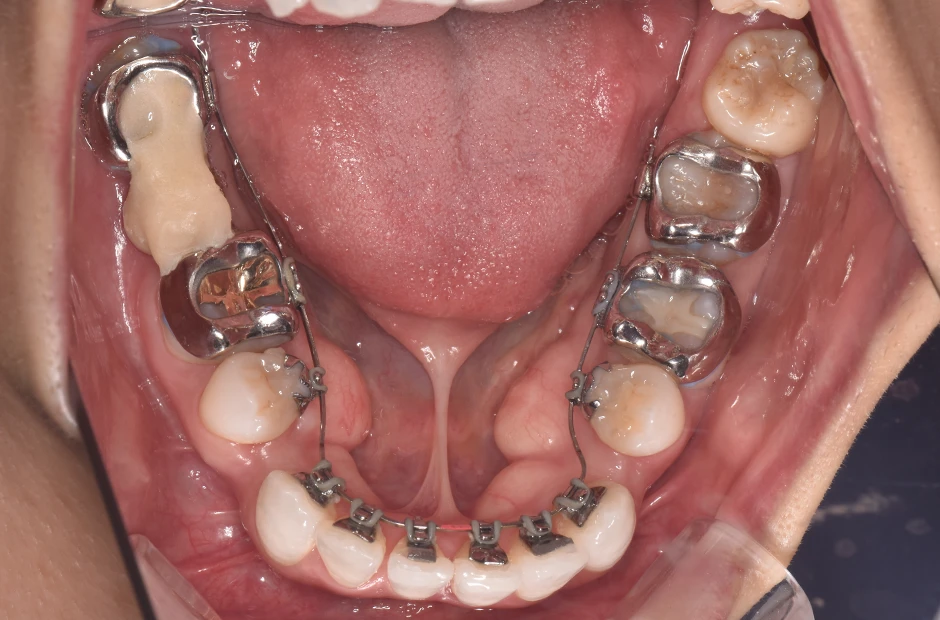

叢生

| 診断名・主訴 | 叢生 |

|---|---|

| 年齢・性別 | 43歳・女性 |

| 治療期間・回数 | 2年7か月 27回 |

| 治療に用いた主な装置 | 舌側矯正 |

| 抜歯部位 | 両顎4,4 |

| 治療費 | 100万円(税抜) |

| リスク・副作用 | 装置による違和感・疼痛・歯肉退縮・歯根吸収・虫歯のリスクなど |

治療前

治療後